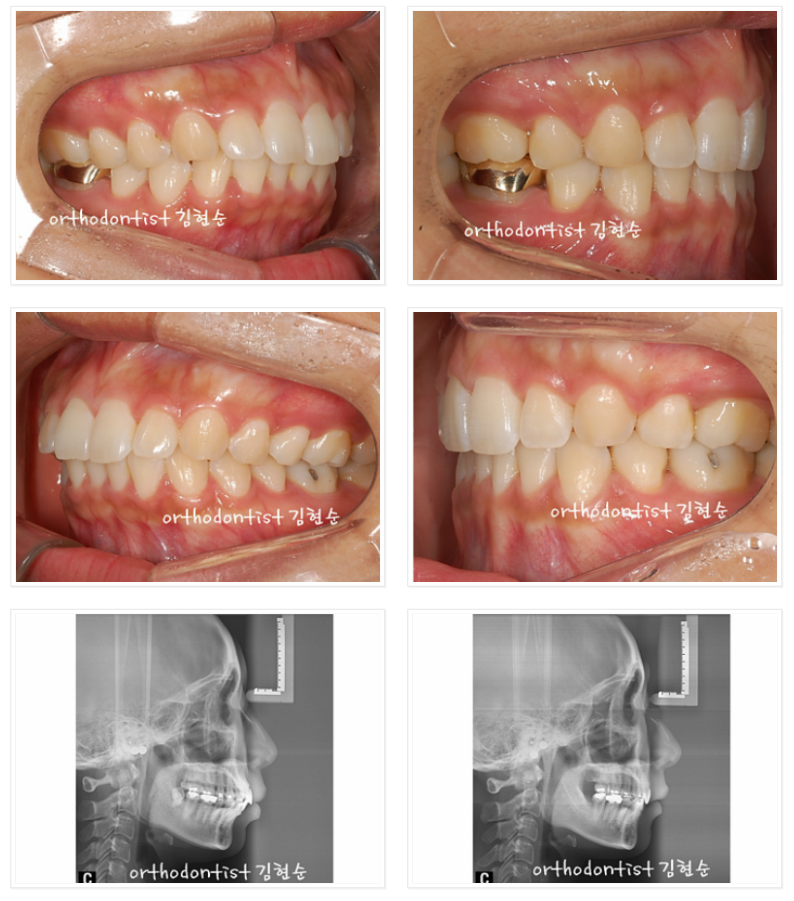

이 분은 앞 얼굴 및 전체적인 인상이 정말 아름다워지셨습니다.

다만 공개된 곳에서 정면 얼굴을 올리시는 것은 결례인 것 같아

차마 올리지 못해 아쉽네요.^^;